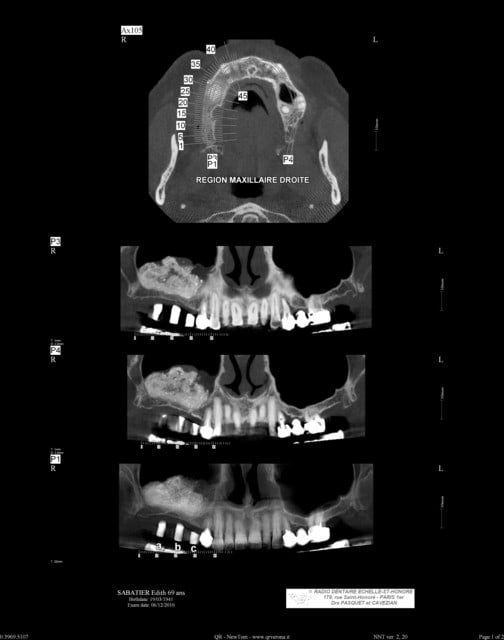

patiente ayant été implantée il y a 12 jours et toujours mal

le sinus lift a été pratiqué il y a 8 mois

Aspect lacunaire du biomat au scanner = sucre mouillé infecté...car non vivant et non vascularisé

bon je m'en doutais un peu que ça venait des lacunes dans le bio oss

Toujours est il qu'avec un agrandissement on verrait sûrement plein de petites lacunes , mais déjà là les grosses...